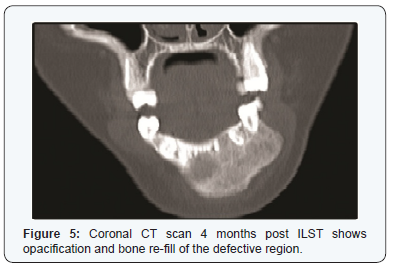

Four months post- ILST, there was no mobility of the teeth No. 33 & 34, harder mass on palpation and CT scan (Figure 5& 6) have shown increased opacity and defect refill.